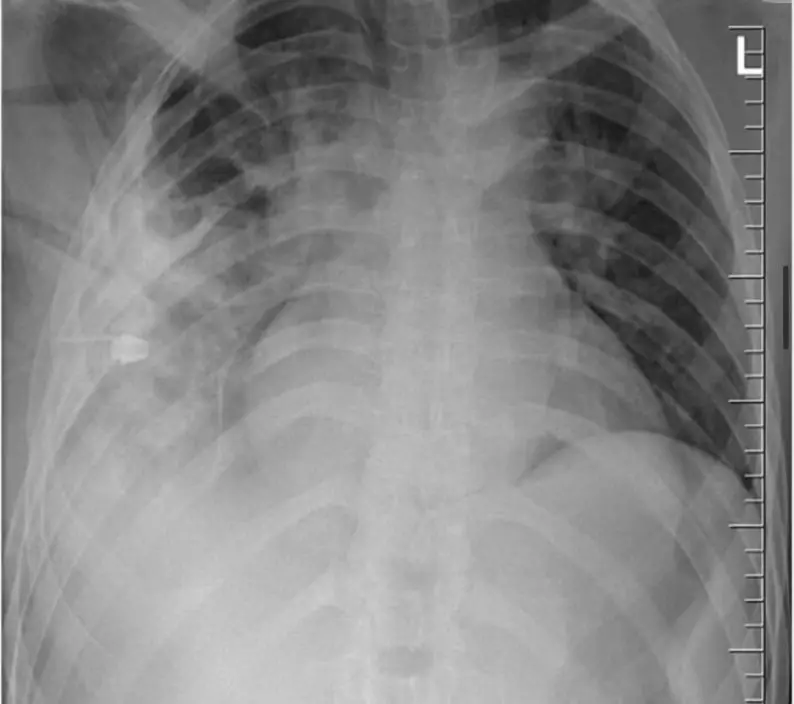

綜合外媒報導,非洲坦桑尼亞出現一宗罕見醫療案例,一名44歲男子因右側乳頭附近長期流出惡臭膿液而求醫。醫療團隊檢視後發現,患者右乳頭下方有明顯膿液排出,周邊組織也出現硬化情況,但除相關部位外,整體健康狀況尚屬正常,並無胸痛、呼吸困難或發燒等典型感染症狀。

醫生隨後為男子安排X光檢查,結果發現胸腔內竟藏有一件利刃狀金屬異物,自肩胛骨位置刺入,四周被膿液及壞死組織包圍,令醫療團隊大為震驚。在醫生追問下,患者回憶起 8 年前曾捲入一場激烈衝突,當時臉部、背部、胸部及腹部均遭多處刀傷。然而,由於當地醫療資源匱乏,他僅接受表層傷口縫合,並無進行深入檢查,之後多年也未曾出現異常症狀。